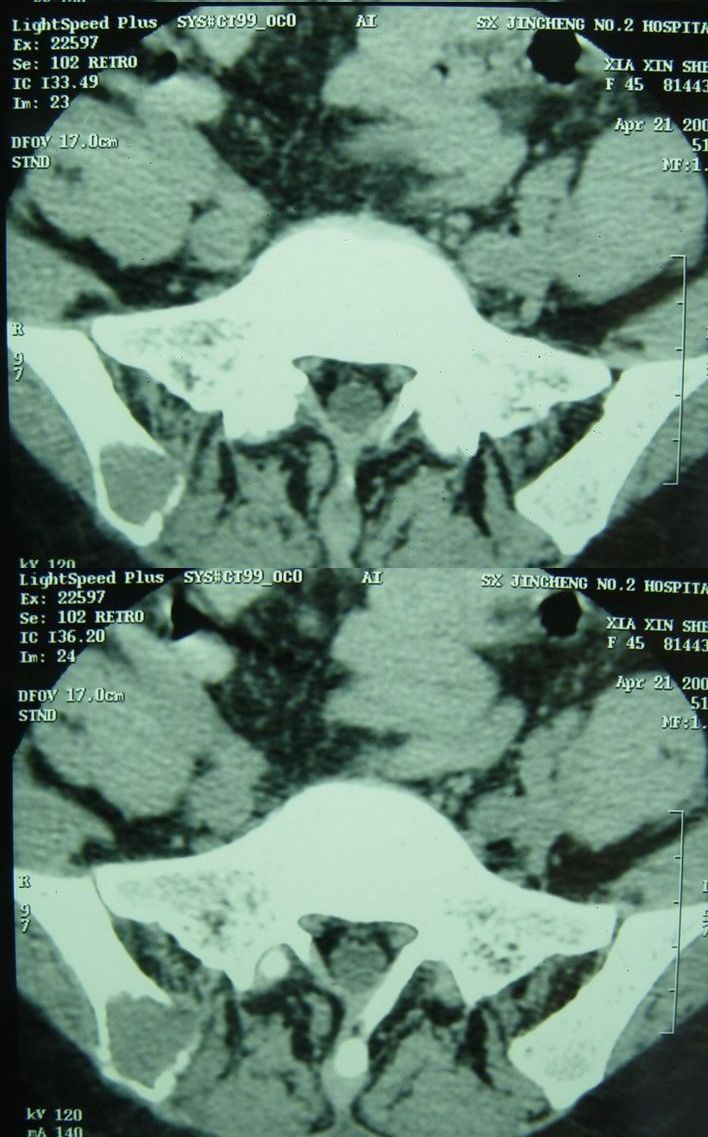

标题: CT13002:女,46岁。有子宫肌瘤手术史,现在出现右臀部向腿 [打印本页]

标题: CT13002:女,46岁。有子宫肌瘤手术史,现在出现右臀部向腿

以下是今天的增强片,大家可以看看:

右侧髂骨后缘囊状膨胀性骨质改变,无明显骨间隔,周围无明显硬化及骨膜反应,周围软组织无异常,相邻骨组织密度增高,考虑:动脉瘤样骨囊肿可能,要注意与骨巨细胞瘤及转移瘤鉴别。

右侧髂骨膨胀性骨质破坏区 囊内密度尚均匀 骨巨细胞瘤可能性大 动脉瘤样骨囊肿不除外 建议mr观察囊内成分明确诊断 左侧附件区包裹性积液

该病人今天做了增强,右侧髂骨病灶明显强化。

临床和影像学表现:女性患者46岁,有子宫肌瘤手术病史。影像所见可见残余宫颈部分,左右附件未见新生物;右髂骨翼后端囊状膨胀性骨破坏,囊性部分感觉有强化(楼主标上增强前后的ct值就很好了),未见明确的液—液平面,周边硬化不明显或轻度硬化。

分析:患者年龄46岁,没有明确外伤病史,病变呈膨胀性骨破坏,囊性部分未见明确的液—液平面,周边硬化不明显。综合分析该病例比较符合骨巨细胞瘤,不太符合动脉瘤样骨囊肿。

诊断:1、首先考虑骨巨细胞瘤;2子宫肌瘤术后改变